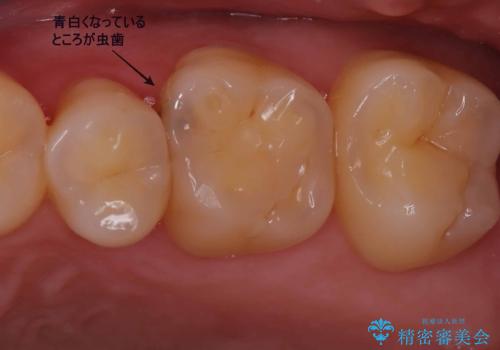

目立つ銀歯と露出した歯根 セラミックでの審美歯科治療